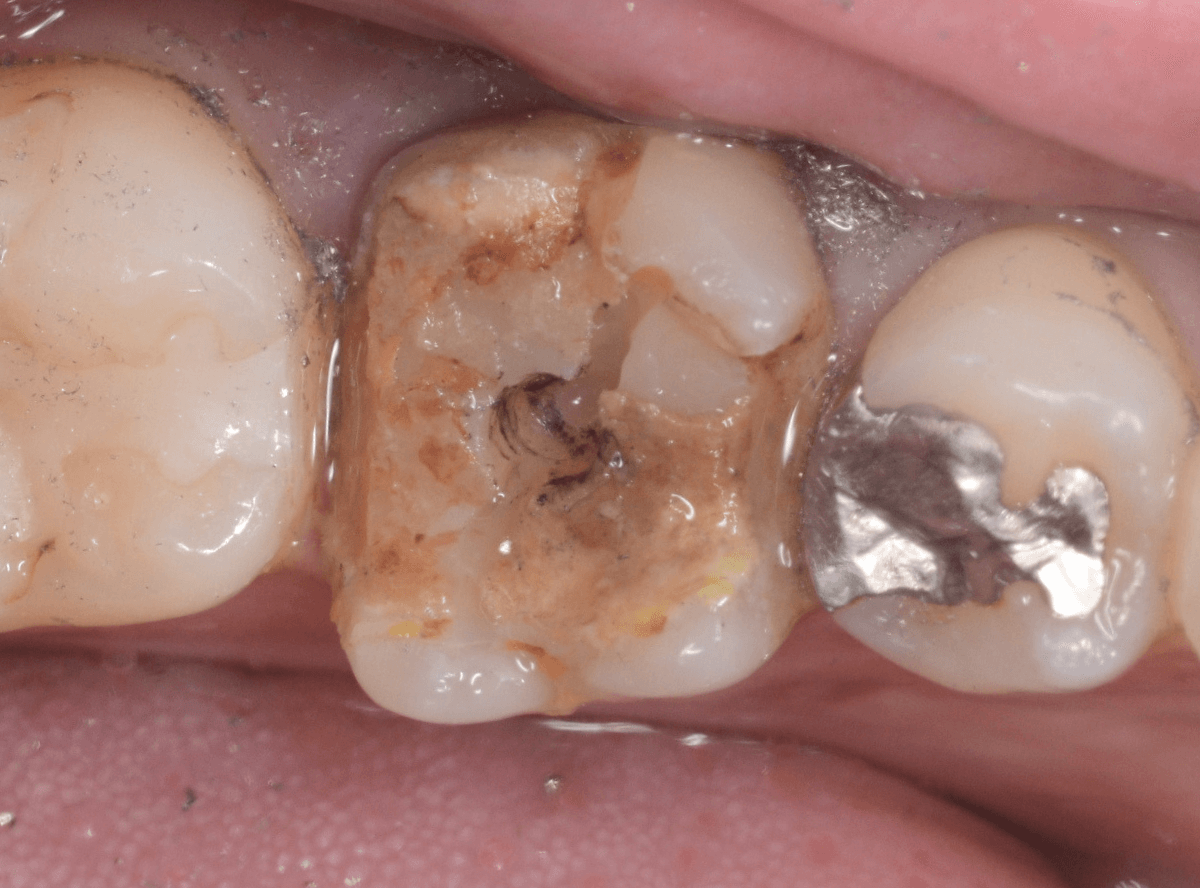

虫歯を全て除去しました。

幸い、あまり多く削る事なく進められたので良かったです。

手前の歯のつめ物も外します。

こちらもお薬が入っていますが、外して中を調べます。

こちらは中も問題なかったです。